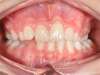

Cas 4 : Description

Chevauchement sévère. Traitement multibague sans extraction.

Avant

Après